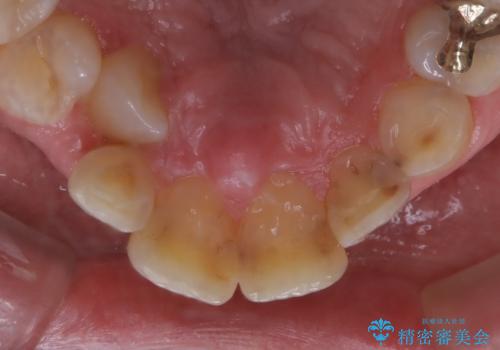

- 被せ物の治療が終了したためメンテナンスに入る前に全体的なチェック・クリーニングを行いました。

歯科衛生士による専門的なクリーニングPMTC(保険外治療)60分コースを行いました。

専門的な機械・材料を使用して徹底的に汚れを取り除きました。